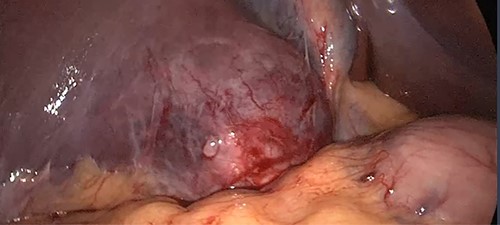

The patient was admitted to the hepatobiliary service and underwent a diagnostic laparoscopy, which revealed the location of the hepatic abscess to be in segment 6 of the liver (Fig. 5). The abscess was unroofed and evacuated, revealing a free-floating bullet that was promptly extracted (Fig. 6). Further exploration of the cavity after evacuation of the abscess revealed a small duct leaking bile, which was sutured and clipped.